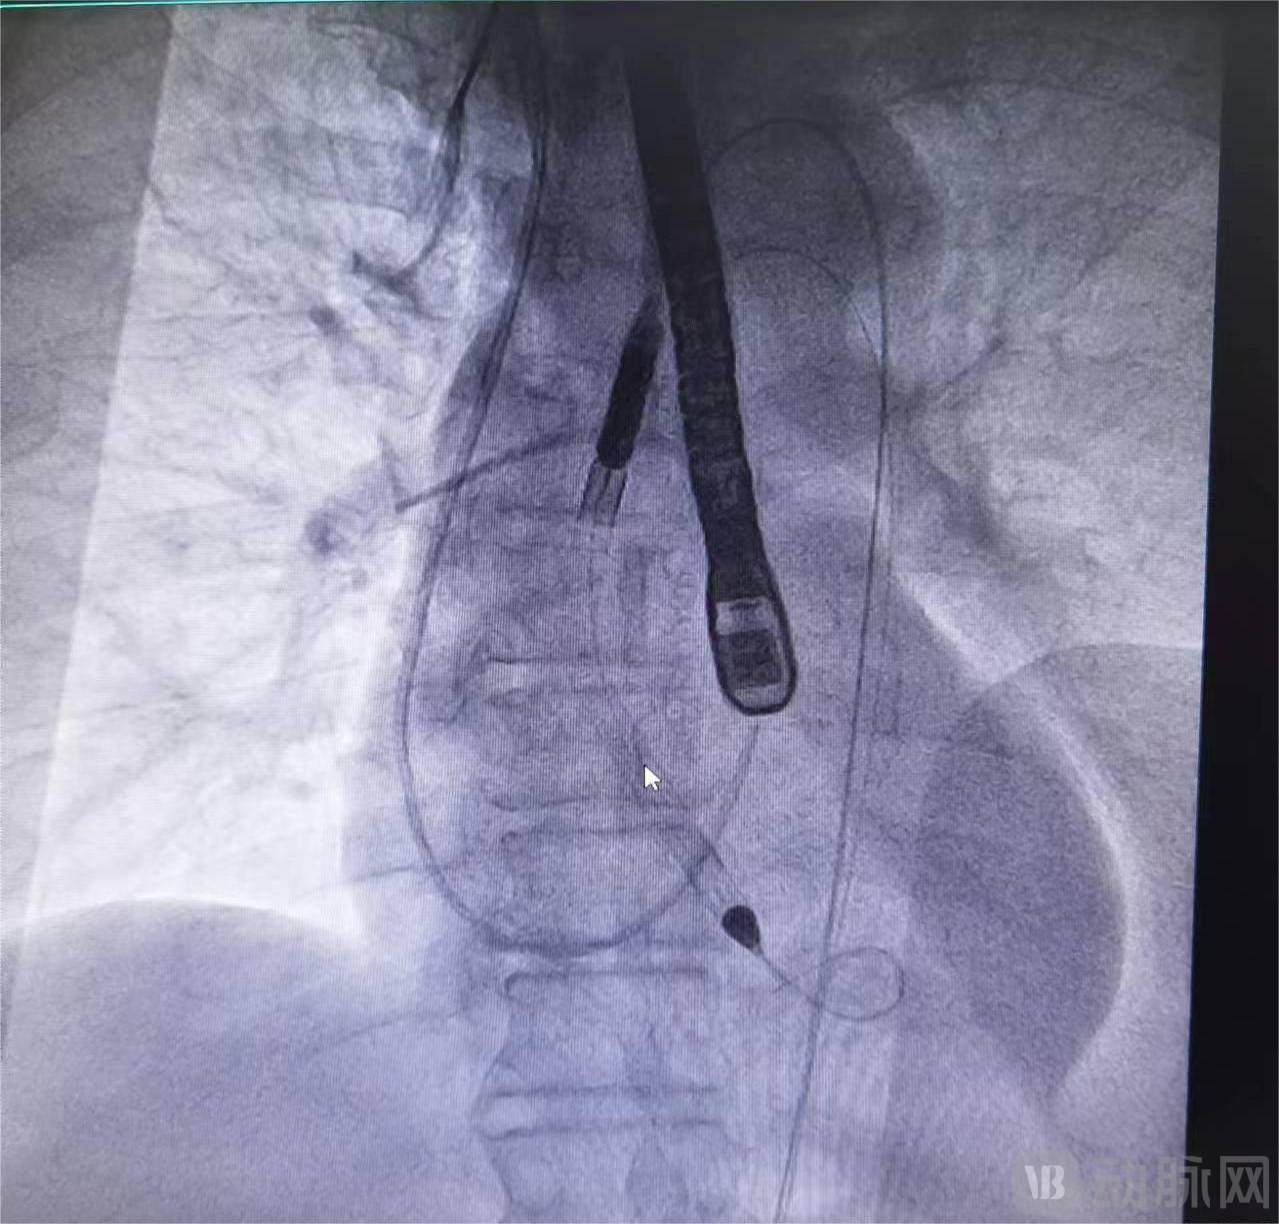

经福建协和医院多学科专家联合会诊,最终决定先利用pVAD纠正心源性休克,待患者情况稳定后行血管再通手术。手术过程中,陈良万教授、李虔桢副主任医师等专家经股动脉穿刺,将pVAD导管泵置入患者左心室,患者血流动力学逐渐稳定。随后顺利开展血管再通手术。术后,患者各项生命指征保持平稳,心脏功能逐渐恢复。经过两周的治疗观察,患者符合出院条件,在院外随访期间整体表现稳定。

pVAD导管泵置入患者左心室